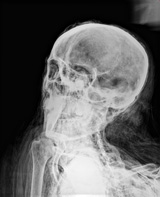

3.

ミイラ(頭部画像(2)) Mummy image (head 2)

このミイラの傾いた頭部画像は,ミイラのあごから首のラインにかけて詰め物を確認した。両眼に見られる乾燥した詰め物は,ミイラ化のために残されたと考えらる。

撮影および画像提供: フィールド博物館 |